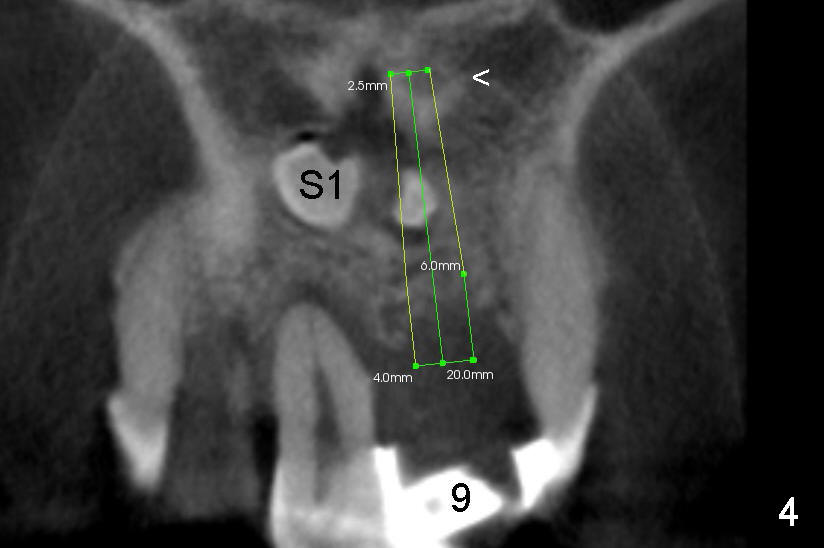

A 41-year-old man has poor dentition (Fig.1: #12 immediate provisional). It appears that #10 is congenitally missing. A temporary bridge is fabricated (Fig.1: #8-11) when #9 is reportedly extracted. Recently bonding between #9 pontic and #11 detaches. The bridge is loose (Fig.2). The tooth #8 is periodontally compromised (Fig.3,5: CT sagittal and coronal sections, respectively).

Treatment plan is to extract two supernumerary teeth (S1,S2) and #8, bone graft (mainly S1,2 sockets, and #8 buccal for cosmetics) and place immediate implants at the sites of #8 and 9. Long implants (20 mm) are to be used to engage into the two bone segments, coronal and apical to the S1,2 sockets (Fig.5,6). Since the bone segment apical S1,2 sockets is mainly cortical (arrowheads in Fig.3-6; lamina dura and nasopalatine canal), the two implants are expected to be stable. A palatal incision is going to be made to expose S1,2, as one of them (S2) is more or less palatal (Fig.6). Here is surgery.